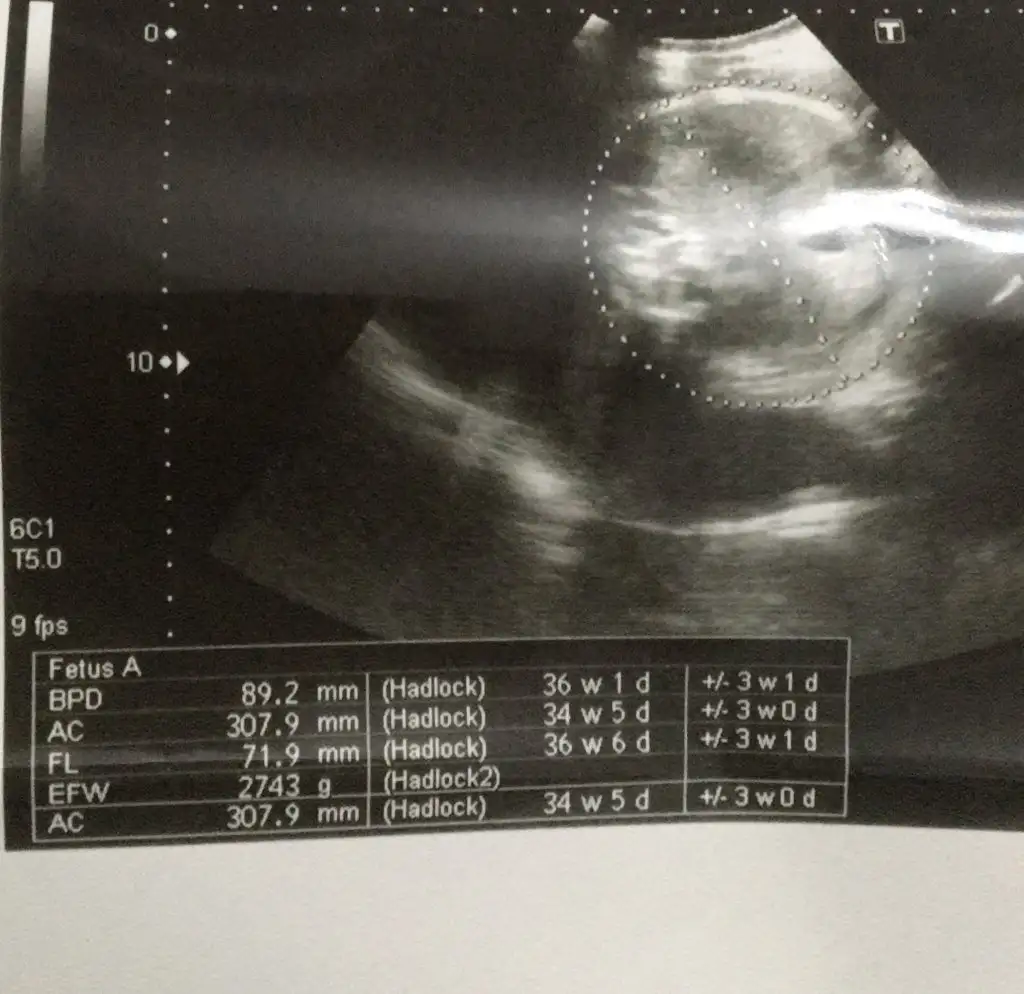

Haftasıyla uyumlu sorunsuz bir ölçüm görünuyor canım sen neyden süphelendinKızlar ya surda ki değerler normal mi ?

Karın çevresi 10 gün geri benmde iki hafta geriKızlar ya surda ki değerler normal mi ?

Ama kilo alıyosa öyle çok büyük bi sorun değil hiç sıkma canını ben çok araştırdım biraz zayıf olurlarmış ki 10 gün çok değil zaten boyu da uzun maşallah haftasına göreKızlar ya surda ki değerler normal mi ?

Karın bölgesi geriden geliyor ultrasona göre ama bu son haftalardaki ölçüm çok doğru olmuyormuş genelde çoğu bebeğe karnı geriden geliyor diyolar. Genel olarak haftasıyla uyumlu görünüyorKızlar ya surda ki değerler normal mi ?

Uzun ince bir bebiş canım seninkiKızlar ya surda ki değerler normal mi ?